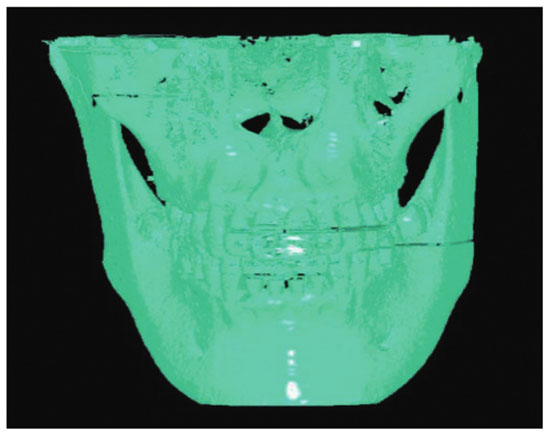

采用医学界常用软件MicroDicom Viewer进行三维重建开展参照实验。MicroDicom Viewer三维重建效果如

图 9. 用MicroDicom Viewer对口腔CBCT数据进行重建的效果图

Fig. 9. Reconstruction result of oral CBCT data using MicroDicom Viewer

由

对比